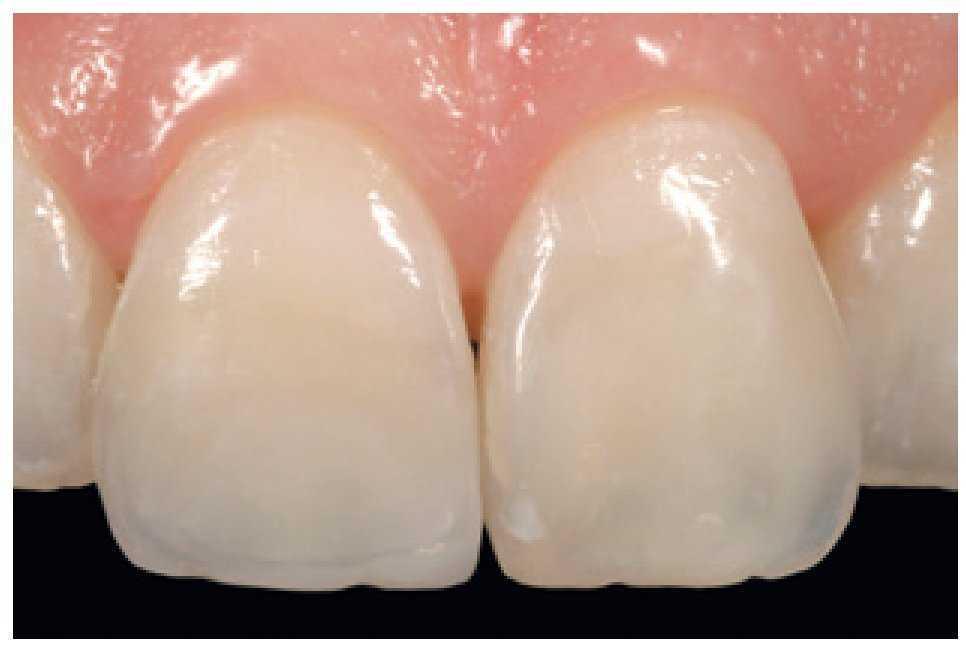

Figura 49 Vista de las restauraciones y los elementos rehidratados después de 72 horas.

Figura 50 Buena integración estética de las restauraciones y salud de los tejidos periodontales 30 días después del tratamiento.